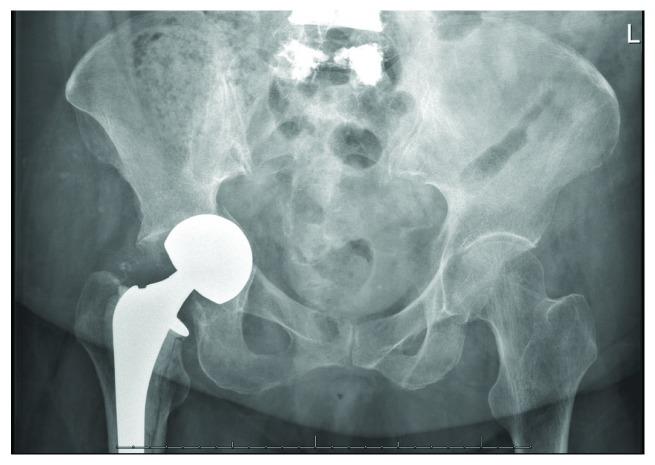

Both hemiarthroplasty and total hip arthroplasty have been well described as effective methods of management for displaced femoral neck fractures in the elderly. Acetabular erosion is a common long-term complication of hemiarthroplasty. We present a case in which rapid acetabular erosion occurs within weeks of hemiarthroplasty, ultimately leading to an acetabular fracture and need for revision to total hip arthroplasty. Early and rapid acetabular erosion following hip hemiarthroplasty has not been well documented in current literature. It may lead to acetabular fracture and may be secondary to infectious causes. If encountered, an infection workup should be initiated.

半髋关节置换术和全髋关节置换术均已被充分描述为治疗老年人移位型股骨颈骨折的有效方法。髋臼侵蚀是半髋关节置换术常见的长期并发症。我们报告一例半髋关节置换术后数周内发生快速髋臼侵蚀的病例,最终导致髋臼骨折并需要翻修为全髋关节置换术。目前文献中尚未充分记录髋关节半置换术后早期快速髋臼侵蚀的情况。它可能导致髋臼骨折,可能继发于感染原因。如果遇到这种情况,应启动感染检查。